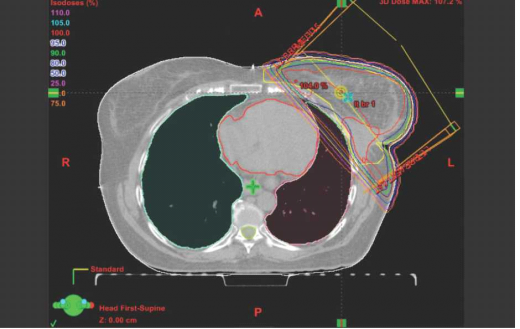

ניתן לרפא חלק ניכר מהנשים שלקו בסרטן שד, מבלי לפגוע בלב כתוצאה מהקרינה. עם זאת, לעיתים, כתוצאה מהתלות באנטומיה (תמונה מספר 1). היות שהלב נמצא במיקום קדמי (Anterior), מתן קרינה לשד ולמיקום הגידול המקורי מבלי להקרין חלק מהלב הוא בלתי אפשרי. במקרים כאלה יש לנסות לדחוק את הלב אחורנית (Posterior) ולהרחיקו מדופן בית החזה באמצעות נשימה עמוקה, שיכולה להזיזו משדה הטיפול למרחק של סנטימטר (ס"מ) וחצי לאחור, ולהוות חייץ המגן עליו (תמונה מספר 2).

הבעיה נעוצה בכך שאף מטופלת אינה יכולה לעצור את נשימתה לדקה - הזמן הנדרש למתן שדה קרינה. מסיבה זו יש לסנכרן בין מתן הקרינה במאיץ הקווי לבין נשימותיה של המטופלת, ולתת את הקרינה עצמה רק בפאזת השאיפה (Inspirium) העמוקה. מערכת כזו, המסנכרנת בין תנועות הנשימה לקרינה עצמה, נמצאת כיום (נכון לשנת 2015) במספר בתי חולים בארץ ואין ספק כי השימוש בה משפר את האפשרות לתת לחולות טיפול מיטבי ללא פגיעה בלב. מערכת זו נקראת RPM (Real time Position Management) והיא אחראית על מתן הקרינה בזמן השאיפה בלבד, כדי לוודא מיקום מרוחק של הלב מאזור הקרינה. המטופלת נדרשת לשתף פעולה, להבין את הנדרש ממנה ולנשום לפי הוראות המחשב, כדי שניתן יהיה להקרין את האזור בפאזת הנשימה הבטוחה.

במרכז רפואי ע"ש חיים שיבא, תל השומר, טופלו עד שנת 2015, 230 נשים בטכניקה זו בהצלחה. מתוך 260 נשים שביצעו בדיקת CT במטרה לבדוק אם ניתן לטפל בהן בשיטת RPM, ל-25 מהן לא נמצא יתרון בביצוע הטיפול הקרינתי בשאיפה [קרום הלב (Pericard) צמוד לדופן בית החזה הקדמי], וחמש נשים לא הצליחו לשתף פעולה ולבצע את הוראות הנשימה בתזמון הנדרש.

עם זאת, במחקר שנערך בשיבא, בהשוואה בין תכניות טיפול עם ובלי RPM, נמצא הבדל ברור ומובהק סטטיסטית לטובת שיטת RPM, לפיה רוב נפח השדיים עובר הקרנה מבלי לוותר על חלקו המדיאלי, בשל מיקום הלב. כמו כן, נמצא שיפור חד-משמעי בנפח הלב שקיבל קרינה מועטה בלבד, בשתי הטכניקות[2].